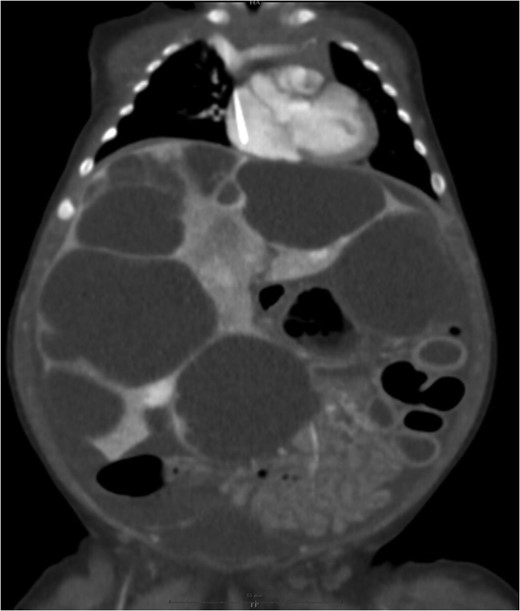

Medical treatment was started immediately with intravenous corticoids (2 mg/kg/day) accompanied with beta-blockers (propranolol 2 mg/kg/day). Ultrasound and CT scans performed after 6 months showed scattered liver parenchymal invaded by multiple enlarging cysts varied in sizes and shapes and causing severe abdominal compression (Fig. 3).

Liver parenchyma invaded by multiple enlarging cysts varied in sizes and shapes.